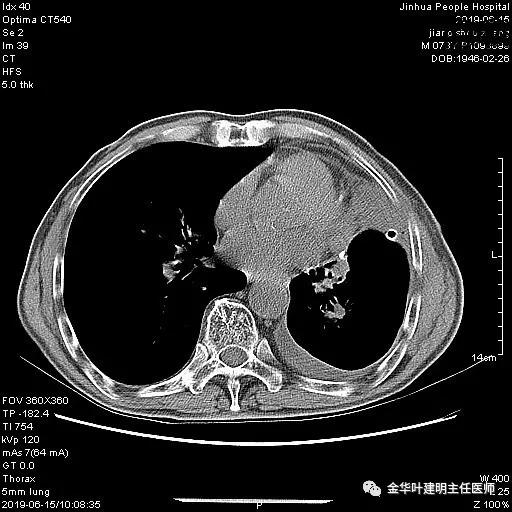

6.15上午:24小时胸管引流出血性液250ml;复查胸部CT示:

6.16上午:24小时引流量110毫升;

6.17上午:24小时引流量90毫升;